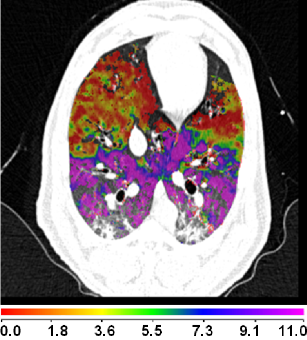

Figure 8(a) shows a comparison between the registration-derived indices of ventilation and the Xe-CT estimated sV in cube-shaped regions of interest for animal D. The corresponding Xe-CT regions in the are divided into about 100 cubes. Figure 8(b) is the Xe-CT estimate of sV. Figure 8(c), (d), (e) are the corresponding registration ventilation measures SAJ, SACJ and SAI. The regions with edema are excluded from the comparison. Figure 8(b) to (d) all show noticeable similar gradient in the ventral-dorsal direction. Notice that the color scales are different in each map and are set based on the range of values from the appropriate plot in Fig. 9.

Figure 9 shows scatter plots comparing the registration ventilation measures and the Xe-CT ventilation sV in all four animals. The SACJ column shows the strongest correlation with the sV (average ). The SAJ, which is directly related to Jacobian as , also shows good correlation with the sV (average ). The intensity-based measure SAI shows the lowest correlation with the sV (average ).